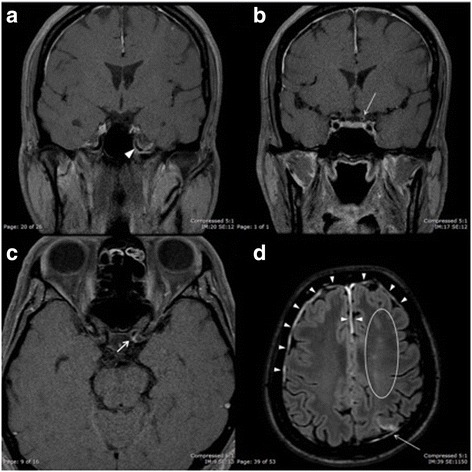

Magnetic resonance imaging (MRI) of the brain with gadolinium injection revealed early subacute left anterior cerebral artery/middle cerebral artery watershed infarction, early subacute left middle cerebral artery/posterior cerebral artery watershed infarction, and marked pachymeningeal thickening with enhancement of the bilateral cerebral convexities (Fig. 2d). Diffusion weighted imaging (DWI) of the brain showed restricted diffusion involving gray-white matter of the left parietal lobe and centrum semiovale. Moreover, enhancement and luminal narrowing of the petrous and supraclinoid left internal carotid artery (ICA) were observed (Fig. 2a–c). The bilateral optic nerves showed a normal size and signal intensity. Magnetic resonance angiography (MRA) revealed luminal narrowing from the distal cervical left ICA extending to the supraclinoid left ICA. The patient was treated with aspirin. Echocardiography and electrocardiography showed normal results.

Fig. 2.

Magnetic resonance imaging of the brain with gadolinium injection. a, b Coronal T1-weighted images with gadolinium injection showing enhancement and luminal narrowing of the petrous (arrowhead) and supraclinoid (arrow) left internal carotid artery. c Axial T1-weighted image with gadolinium injection showing enhancement and luminal narrowing of the supraclinoid (arrow) left internal carotid artery. d Axial fluid attenuation inversion recovery (FLAIR) image with gadolinium injection showing early subacute left anterior cerebral artery/middle cerebral artery watershed infarction (area within the circle), early subacute left middle cerebral artery/posterior cerebral artery watershed infarction (arrow), and marked pachymeningeal thickening with enhancement of the bilateral cerebral convexities (arrowheads)